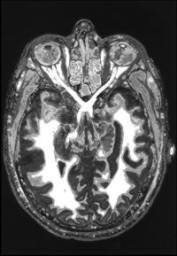

La scienza incontra un grosso ostacolo quando passa dallo studio delle funzioni cognitive all’esperienza cosciente, anche se lo sforzo intrapreso è immenso. Attualmente il campo di maggior importanza è quello della ricerca dei correlati neurali degli eventi mentali: i paragrafi Materiali e Metodi – che nei lavori scientifici seguono l’Introduzione e precedono Risultati e Discussioni – si sono arricchiti di nuovi strumenti che forniscono sofisticate immagini del cervello in azione, dotate di un potere altamente suggestivo, come le tecnologie PET, SPECT e fMR.

Grazie ad esse si è riusciti a riportare il percepire e il ricordare – ma anche il contemplare e il pregare[3] – all’attività di precise aree corticali interconnesse. Poi ci sono i dati provenienti dalle stimolazioni della corteccia a cervello scoperto: i pazienti, svegli, sono “pizzicati” in aree specifiche da microscariche elettriche, e riferiscono di rivivere scene-flash ed episodi di molti anni prima[4]. Impressionanti sono anche le prove empiriche di sincronizzazioni alla frequenza di 40 Hertz dell’attività di gruppi di cellule distanti tra loro, che risuonano insieme nel momento preciso in cui riconosciamo un volto o fondiamo tutti i dati percepiti in una scena unitaria[5].